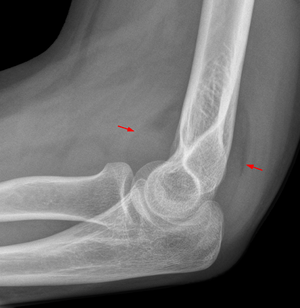

- Are the fat pads normal?

- A visible ant. fat pad is normal but if displaced anteriorly (Sail sign) it is abnormal

- A visible post. fat pad is always abnormal